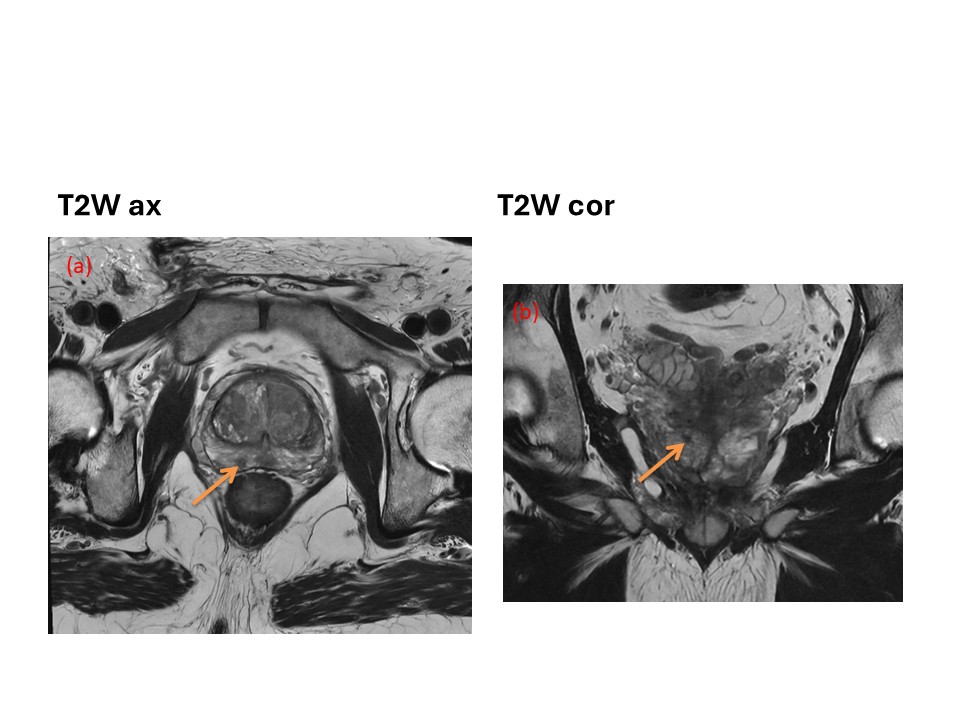

T2-weighted images in the axial (a) and coronal planes (b) demonstrate a small lesion (5 mm), of low signal intensity, located in the peripheral zone of the prostate gland (arrow), PI-RADS: 4.

Final PI-RADS score: 4.

Radical prostatectomy: tumor with Gleason score 4+5, T2a, N0, M0.